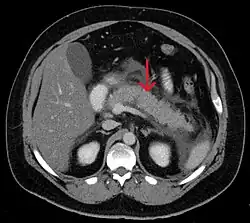

Acute exudative pancreatitis on CT scan

A contrast-enhanced CT scan is usually performed more than 48 hours after the onset of pain to evaluate for pancreatic necrosis and extrapancreatic fluid as well as predict the severity of the disease. CT scanning earlier can be falsely reassuring.[34]